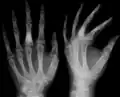

X-ray showing calcified enchondromas localized in finger a 37-year-old patient affected with Ollier disease -

The disease consists of the growth multiple enchondromas which usually develop in early childhood. The growth of these enchondromas usually stops after skeletal maturation.[4] The affected extremity is shortened (asymmetric dwarfism) and sometimes bowed due to epiphyseal fusion anomalies. Bone lesions generally present as cellular during childhood and become more solitary over time. People with Ollier disease are prone to breaking bones (fractures) and normally have swollen, aching limbs. However, many cases of solitary enchondromata go unnoticed due to lack of symptoms. Enchondromas are commonly found in the phalanges, metacarpal, and metatarsal bones in patients of Ollier disease due to the affinity of enchondromas to long tubular bones such as the femur and humerus. A unilateral distribution of bone lesions is usually observed but bilateral distributions or a singular extremity can occur as well. Approximately a third of the cases show some form of physical deformities of bowing or abnormal limb lengthening.

Abnormal bone growth such as shortening or thickening and deformity may be observed in patients of Ollier disease. These bone lesions are visible at birth using radiography but are usually not screened or examined for until clinical manifestations present during early childhood. However, some patients may exhibit no signs of any symptoms.[1] One study found thirteen to be the mean age of diagnosis in patients with Ollier disease. In an X-ray, there would normally be the presence of several homogeneous lesions of an oval or elongated shape with bone edges that are slightly thickened.[3] With age, these lesions may calcify and appear as diffusely minute spots or stippled. Fan-like septations or streaks would be indicative of the presence of several enchondromas. Early detection and consistent and repeated monitoring is important in order to prevent and treat any potential bone neoplasms.